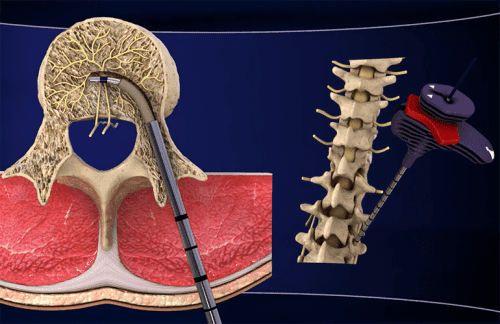

“INTRACEPT” هي إجراء جراحي لا يشبه عمليات العمود الفقري الجراحية التقليدية.

فالجراح أثناء هذه العملية يستخدم جهازًا صغيرًا لقتل العصب المسؤول عن آلام أسفل الظهر.

يستلقي المريض أولًا على وجهه لتلقي التخدير الموضعي في المنطقة الواقعة بين الفقرتين L3 و S1.

بعد ذلك، يتم إدخال إبرة دقيقة جدًا في هذه المنطقة لإيقاف نشاط العصب القاعدي. وذلك لأن العصب القاعدي يرسل إشارات الألم من العمود الفقري إلى الدماغ.

بذلك الإجراء السريع ومن خلال الجراحة الموضعية، يمكن تخفيف آلام أسفل الظهر.

يستخدم هذا العلاج طاقة ترددات راديوية. وهو ما يعني عدم استخدام الجراح للمشرط أثناء الجراحة التي لا تتسبب بأيّة جروح.

يرسل الجهاز طاقة الترددات الراديوية هذه ويشعر المريض بقليل من الحرارة فقط أثناء العملية.

يقوم الجراح بعد ذلك بإزالة الجهاز بسهولة ودون تعريض المريض لأية مضاعفات.

تستغرق العملية بأكملها في الواقع نحو الساعة، ويمكن للمريض أن يعود إلى المنزل مشيًا بعد الانتهاء مباشرةً.